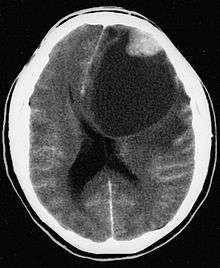

- A CT scan of the brain, and/or an MRI scan of the brain and spine, will be performed. A special dye may be injected into a vein before these scans to provide contrast and make tumors easier to see.